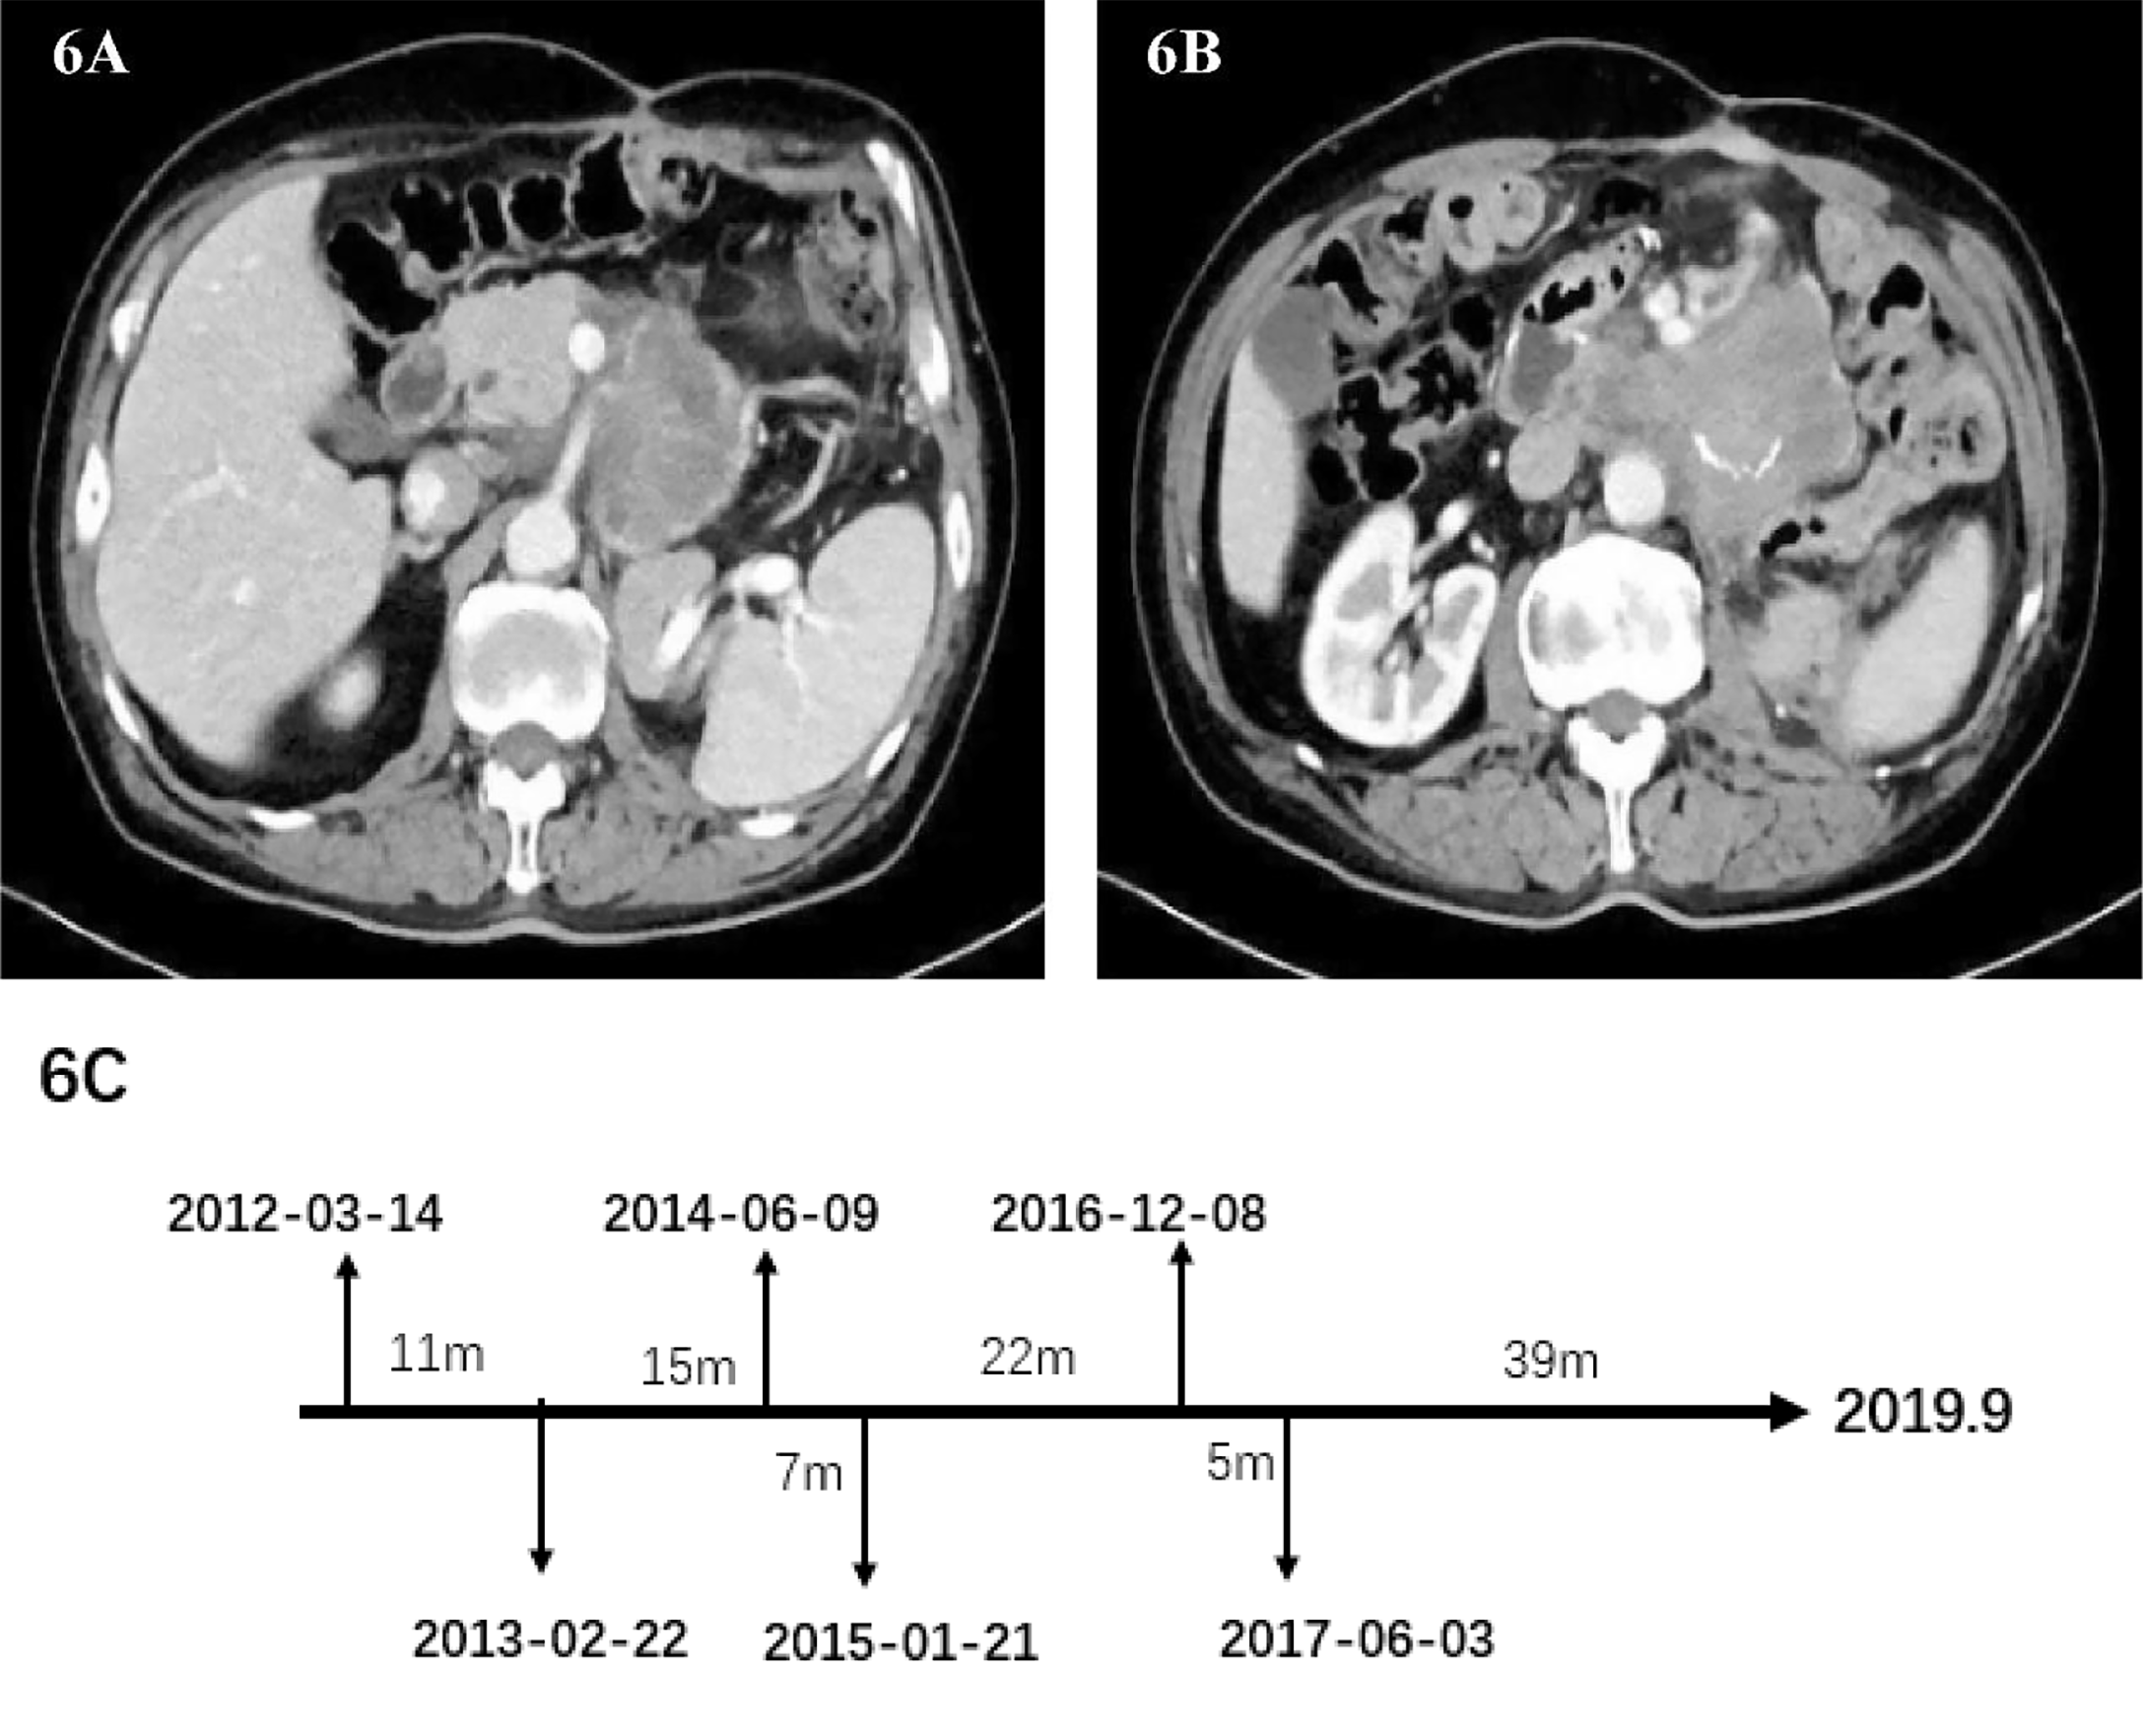

2017-06-03

In May 2017, the patient’s abdominal CT showed the density of retroperitoneal lump-like soft tissue. Considering the possibility of metastasis or tumor recurrence. There is a space-occupying lesion in the abdominal wall incision, which indicates the possibility of tumor metastasis (Figures 6A, B). The surgeon performed the sixth operation which was the final operation on the patient on June 3, 2017. Operation name: Retroperitoneal tumor resection + abdominal wall tumor resection. The history of multiple recurrences and the highly malignant biological characteristics of dedifferentiated liposarcoma made the surgical procedure extremely difficult. The sarcoma wraps the superior mesenteric artery tightly and cannot be peeled off. Considering the risk of continuing surgery, we decided to perform palliative surgery to remove the sarcoma as much as possible. Because the well-differentiated components of the sarcoma are nearly indistinguishable from normal retroperitoneal fat, we surgically removed as much fat as possible in the hope of slowing disease progression. After removing the abdominal wall sarcoma, we performed the incision suture. The abdominal wall incision is closed with a continuous suture using a single-strand absorbable suture. Finally, the incision was reinforced with tension-reducing sutures, and the sutures were removed no earlier than 14 days after surgery. No repair materials or artificial limbs were used in the whole process. Postoperative pathology showed dedifferentiated liposarcoma, some of which showed rhabdomyosarcoma differentiation and invaded subcutaneous tissue. Immunohistochemistry: SMA(-), MyoD1(+), Myogenin(+), CD68(+), S100(-), Ki-67 (+) Approximately 30%. The patient was discharged from the hospital on June 21, 2017. After discharge, he did not receive any radiotherapy or chemotherapy. The patient passed away in September 2019 due to systemic organ failure caused by cachexia (Figure 6C).

Figure 6

(A, B) Abdominal image before the sixth operation. (C) Date chart of operation.